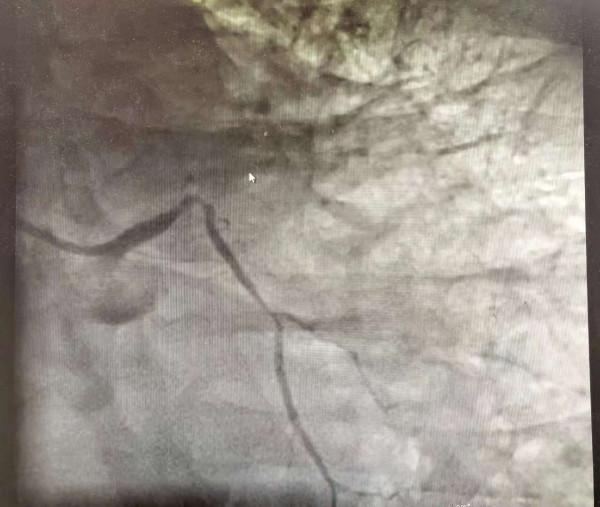

進了手術室做造影一看:心臟上最重要的一根冠狀動脈(前降支)堵了!醫生立即植入支架開通了血管。患者症狀較前明顯緩解,但是醫生卻不敢掉以輕心,返回病房後馬上覆查心電圖,心電圖提示疑似“室壁瘤”形成!